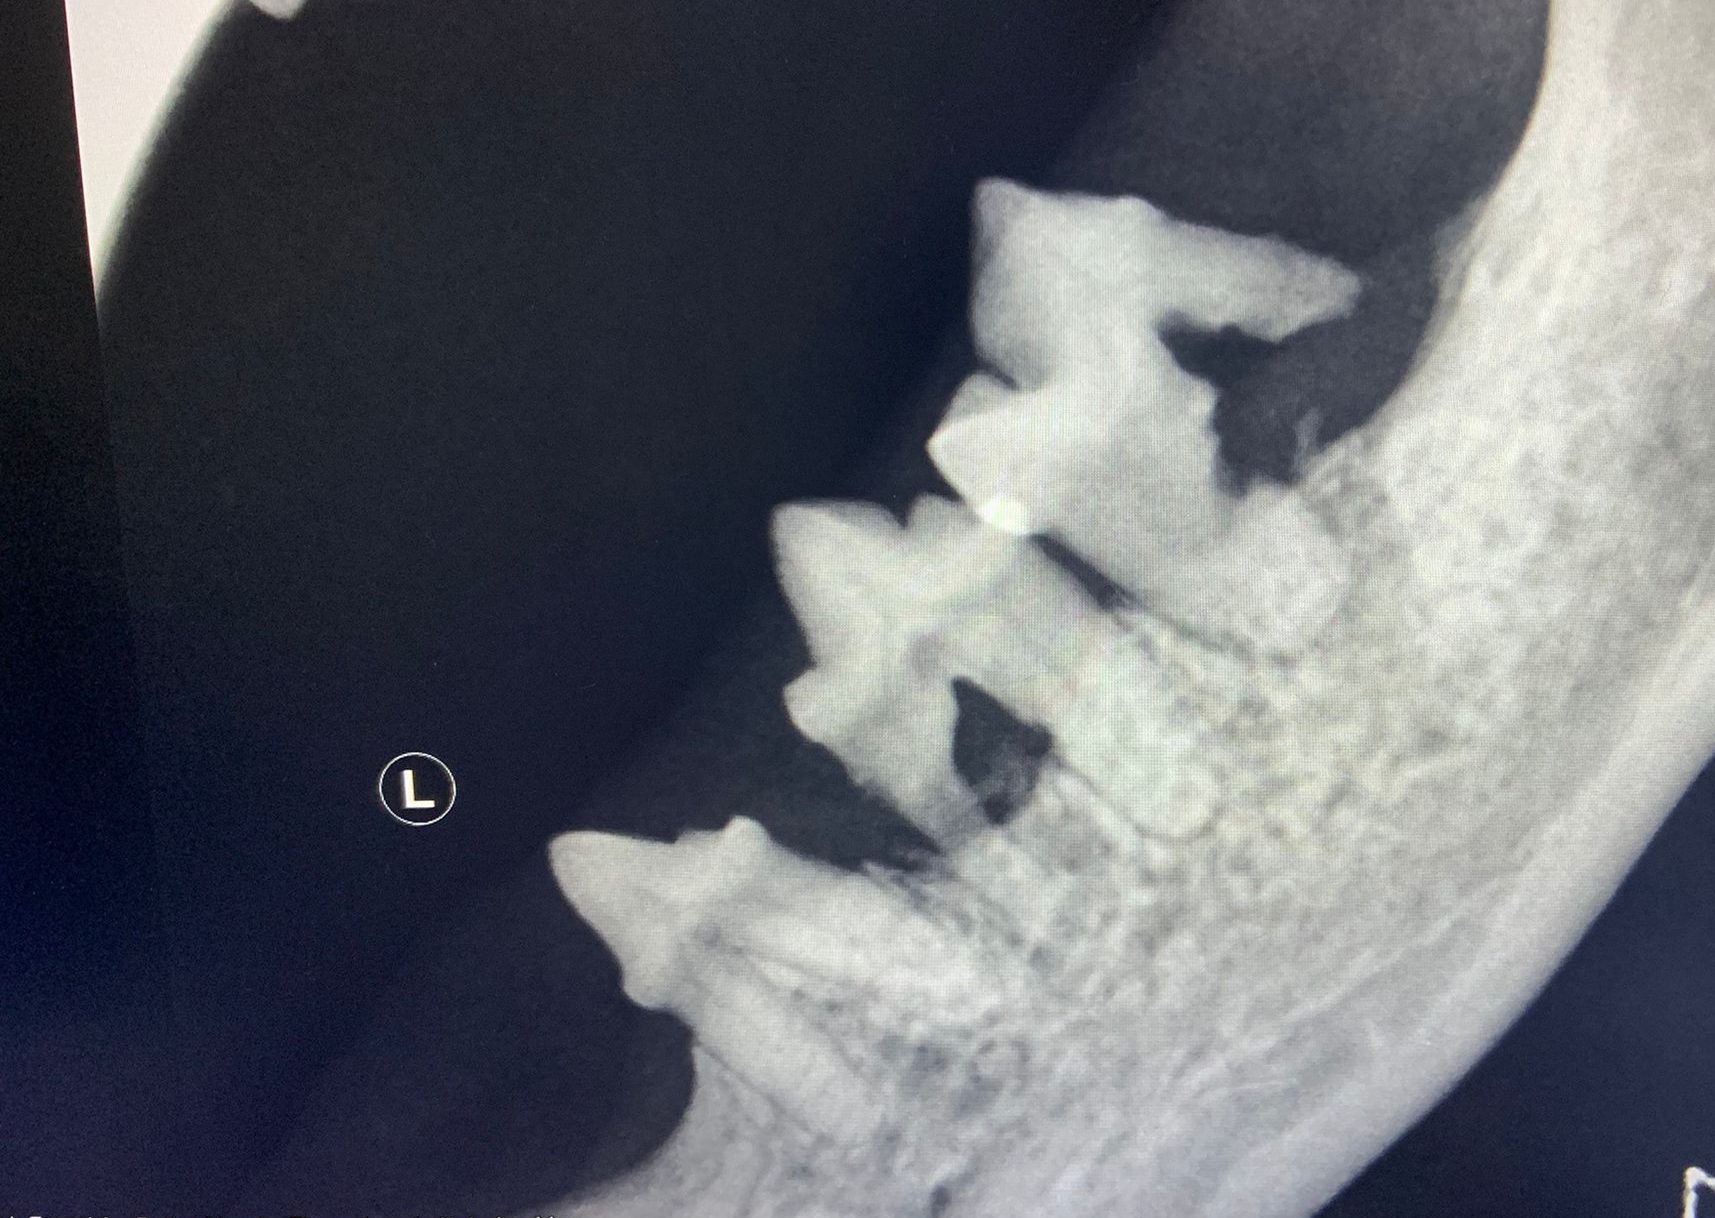

Aus diesem Grund legen wir größten Wert auf die Zahnprophylaxe! Das regelmäßige Zähneputzen bei Hund und Katze bietet hierfür eine solide Basis. Unterstützend empfehlen wir bei unseren Zahnpatienten regelmäßgie professionelle Zahnreinigungen und (Röntgen,-) Kontrolluntersuchungen in Narkose.

Hunde Zahnbehandlung